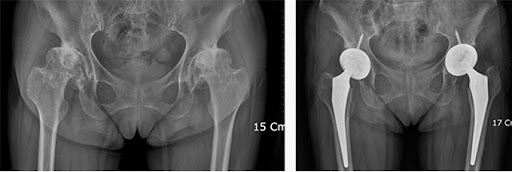

- 인공관절 치환술: 가장 일반적인 고관절 수술입니다. 퇴행성 관절염이나 심한 외상으로 인해 고관절이 손상된 경우, 인공 관절로 대체합니다. 이 수술은 대개 1-2시간 가량 소요되며, 회복이 길어질 수 있습니다.

각 수술 방식에 따라 환자의 상태를 고려한 특화된 치료 계획이 필요합니다. 예를 들어, 인공관절 치환술을 받을 경우에는 십여 주의 회복 기간 동안 물리 치료와 약물 치료가 반드시 포함되어야 합니다. 반면 관절경 수술의 경우에는 초기 회복 단계에서의 가벼운 운동과 체중 부하가 더 강조될 수 있습니다.

- 진단적 검사: 의사가 필요할 경우 정기적으로 X-ray나 MRI를 통해 관절의 상태를 체크할 수 있습니다.